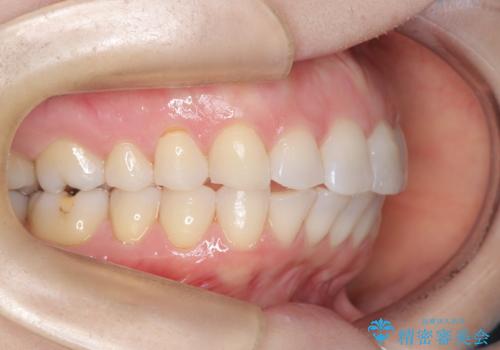

審美装置を用いたワイヤー矯正|非抜歯で歯の凸凹を改善

- 患者様は**歯の凸凹(叢生)**を気にされて来院されました。診査の結果、歯列のスペースが不足しているものの、抜歯をせずに改善できる状態でした。そこで、目立ちにくい審美装置(白いブラケットとホワイトワイヤー)を使用したワイヤー矯正を提案しました。歯列のアーチを広げながら、適宜IPR(歯の幅をわずかに調整する処置)を行い、非抜歯で自然な歯並びへと導く計画を立てました。

治療では、白いブラケットとホワイトワイヤーを使用し、矯正装置が目立ちにくいよう配慮しました。歯列を拡大しながら適切に歯を移動させ、IPRを併用することで、無理なくスペースを確保しました。見た目に配慮しながら、歯の凸凹をスムーズに整え、噛み合わせも改善。患者様からは「装置が思ったより目立たず、歯並びがきれいになって嬉しい」との声をいただきました。